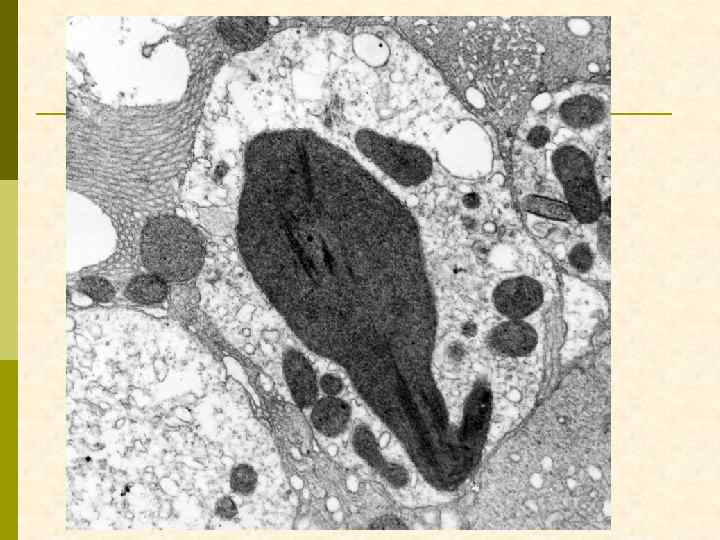

Характерные морфологические признаки ВИЧАН p почки больших размеров p тяжелое повреждение клубочков – коллаптоидный вариант ФСГС p расширение мезангия p гиперплазия и пролиферация подоцитов, аномалия висцерального и париетального эпителия клубочков – дедифференцирование ? ? ? p иммунные депозиты минимальны p атрофия канальцевого эпителия, кистозная дегенерация канальцев с заполнением их белковыми цилиндрами p нередкий тяжелый интерстициальный отек с моноцитарной (лимфоцитарной) инфильтрацией p нередко острый канальцевый некроз p ЭМ: тубуло-ретикулярные структуры в эндотелиоцитах клубочковых капилляров и других сосудов

Характерные морфологические признаки ВИЧ-ассоциированной нефропатии Фокальный сегментарный гломерулосклероз, коллаптоидный вариант.

мембранозная нефропатия + ФСГС, коллаптоподобный

Заключение по ЭМ p В нефробиоптате один частично склерозированный клубочек со значительно утолщенной капсулой, в которой имеются массивные отложения электронно-плотных депозитов и скопления коллагеновых волокон. В неизмененных зонах клубочка гломерулярная базальная мембрана (ГБМ) капилляров неравномерно утолщена с интрамембранной локализацией электронноплотных депозитов. Субэпителиальных и субэндотелиальных депозитов мало. Более массивные депозиты расположены в умеренно расширенном мезангиальном матриксе. В ГБМ коллабированных капилляров обнаружены депозиты смешанного характера с микролипидными включениями. Цитоплазма подоцитов с умеренным набуханием при незначительной микроворсинчатой трансформацией и со слияние малых ножек. HIV-ассоциированные тубулоретикулярные включения обнаружены в цитоплазме многих эндотелиальных клеток гломерулярных капилляров.